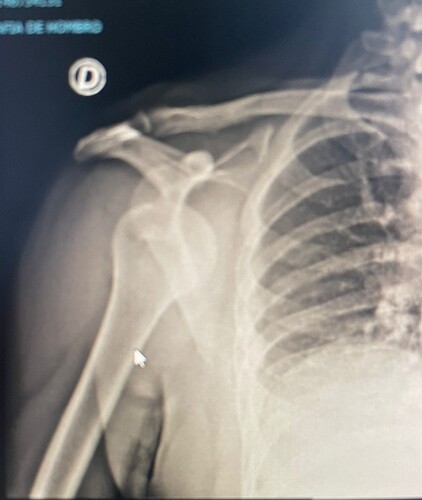

Son has dislocated his shoulder on a business trip abroad. He says he was playing padel .. ![]()